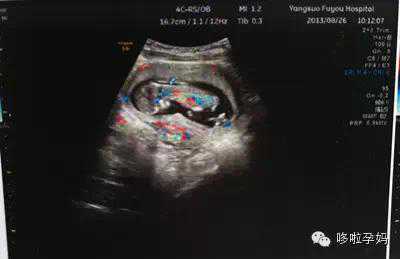

普通B超是黑白的,那彩超就是彩色的吗?其实,彩超并不是彩色的,它只是在黑白B超的基础上,再加上彩色多普勒血流成像,即在B超显示的同时还可以显示出红、蓝两色,来表明不同的血流方向和流速。一般以背离探头的血流显示为蓝色,朝向探头的血流显示为红色。

比起单一的黑白B超,彩色B超功能更多,诊断疾病的途径亦更多,对疾病的诊断亦更明确。其图像分辨力也优于普通黑白B超,尤其对一些恶性肿块的诊断极有价值。在妇科检查中,对于宫外孕医生都会建议使用彩超,但对于一般的妇科体检、子宫肌瘤或是人工流产前的B超普查用普通B超就可以了。